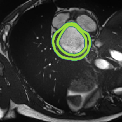

Despite their outstanding accuracy, semi-supervised segmentation methods based on deep neural networks can still yield predictions that are considered anatomically impossible by clinicians, for instance, containing holes or disconnected regions. To solve this problem, we present a Context-aware Virtual Adversarial Training (CaVAT) method for generating anatomically plausible segmentation. Unlike approaches focusing solely on accuracy, our method also considers complex topological constraints like connectivity which cannot be easily modeled in a differentiable loss function. We use adversarial training to generate examples violating the constraints, so the network can learn to avoid making such incorrect predictions on new examples, and employ the Reinforce algorithm to handle non-differentiable segmentation constraints. The proposed method offers a generic and efficient way to add any constraint on top of any segmentation network. Experiments on two clinically-relevant datasets show our method to produce segmentations that are both accurate and anatomically-plausible in terms of region connectivity.